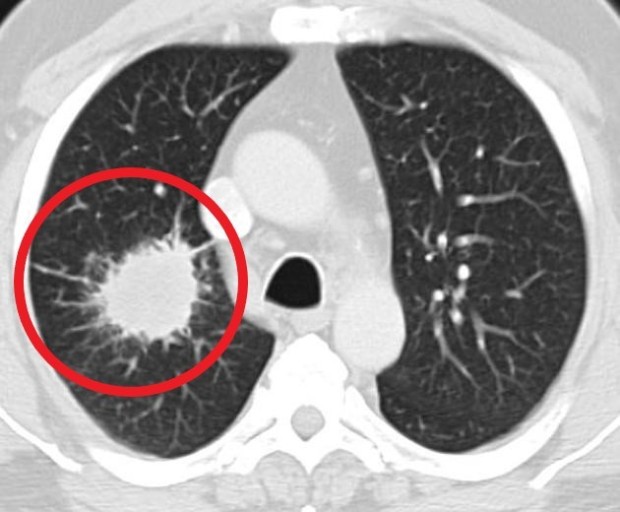

- 정기적인 건강 검진: 위와 같은 증상이 하나라도 나타나면 즉시 병원을 방문하여 흉부 X-ray, CT 촬영 등 검사를 받는 것이 중요합니다.